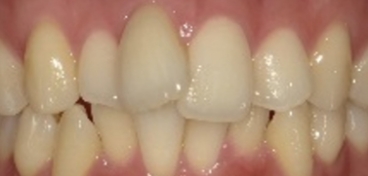

伊藤矯正歯科医院での安定した症例

これに対し伊藤矯正歯科医院では、抜歯を伴う矯正を行ったのちに何も装置を使用しなくて何年か経過しても、かなり安定している症例をみることが多くありました。(「安定調査症例1~4」と当HPの症例集ページ「叢生第3,4症例」をご覧下さい。)そこで治療が終わって数年経過した時点で、資料採得のできた14症例について歯並びの変化を観察しました。